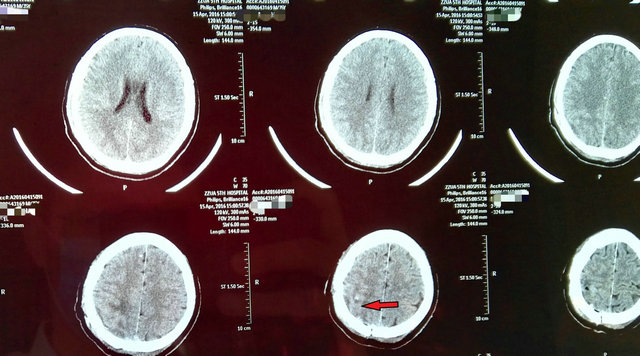

患者李先生今年35岁,一个月前发现左手拿东西不稳了,并且还伴有麻木症状,在多次求医无果后来到郑州大学五附院神经外科一病区。医生经过仔细检查后给李先生诊断为右侧顶叶(中央后回)占位性病变(图1、2)。该病变所处部位十分重要,周围神经、血管复杂,且病变较小,如果术中定位不准,可能会增加副损伤,若稍有不慎可能导致患者偏瘫。

在医院的大力支持下,由神经外科一病区寿记新主任牵头组织了院内多学科会诊,决定采用超声实时引导下脑肿瘤切除的新技术。在神经外科专家以及麻醉、超声专家的共同努力下,寿记新主任亲自主刀,付旭东副主任协助,通过超声精确定位,准确的找到了肿瘤(图3),同时避开了重要的神经、血管,顺利全切病变组织(图4),术后李先生各项生命体征正常,手术获得圆满成功。术后一周,言语、偏瘫逐步恢复正常,影像复查显示肿瘤切除完整,无副损伤(图5)。